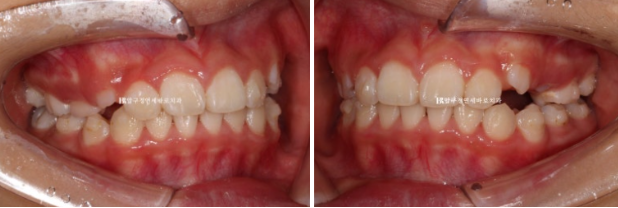

22.08

소아교정을 위해 찾아온 만 9세 어린이 입니다.

위 앞니가 아랫니를 가려서 안 보일 정도로 깊게 물리는 과개교합이고 윗니 돌출이 눈에 띕니다.

한달 반을 기다려서 첫 장치를 낀 것은 22년 9월부터이고 23년 6월까지 9개월간 첫 세트 장치를 모두 낀 후 모습입니다.

23.06

깊게 물리는 과개교합은 해소가 되었고 중심선도 잘 맞습니다.

앞니 돌출은 해소가 되었고 송곳니가 내려오는 중 입니다.